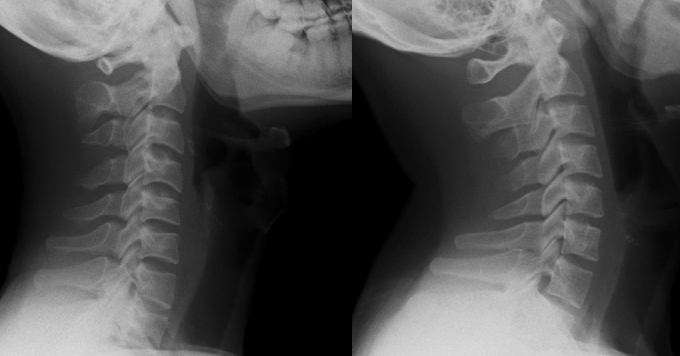

Kết quả chụp cộng hưởng từ cho thấy tình trạng nghiêm trọng: Khối thoát vị không chỉ chèn ép dây thần kinh mà còn chèn vào tủy sống. Ban đầu, chị vẫn hy vọng có thể điều trị bảo tồn để tránh phẫu thuật. Tuy nhiên, sau khi thăm khám chuyên sâu, bác sĩ cảnh báo mức độ chèn ép đã lên tới 2/3 tủy sống, nguy cơ liệt rất cao nếu không can thiệp kịp thời.

Trong tình trạng đau buốt, đầu lệch hẳn sang một bên, tay co quắp, chị H. cùng gia đình phải sớm ra quyết định mổ hay điều trị nội khoa. Cuối cùng, hai vợ chồng quyết định phẫu thuật. Ca mổ diễn ra ngay sau đó và điều khiến chị bất ngờ là ngay khi tỉnh dậy, cơn đau cổ vai gáy gần như biến mất hoàn toàn.

Chị H. được thông báo đĩa đệm đã vỡ thành nhiều mảnh, nếu không phẫu thuật thì không có phương pháp nào có thể phục hồi.

Bên cạnh đó là tình trạng co cứng cổ hoặc lưng, tay chân yếu, khó cử động - những phản ứng tự bảo vệ của cơ thể khi tủy sống bị chèn ép. Vì vậy, các bác sĩ buộc phải chỉ định phẫu thuật. Trong quá trình mổ, bác sĩ ghi nhận khối thoát vị rất lớn và phức tạp.